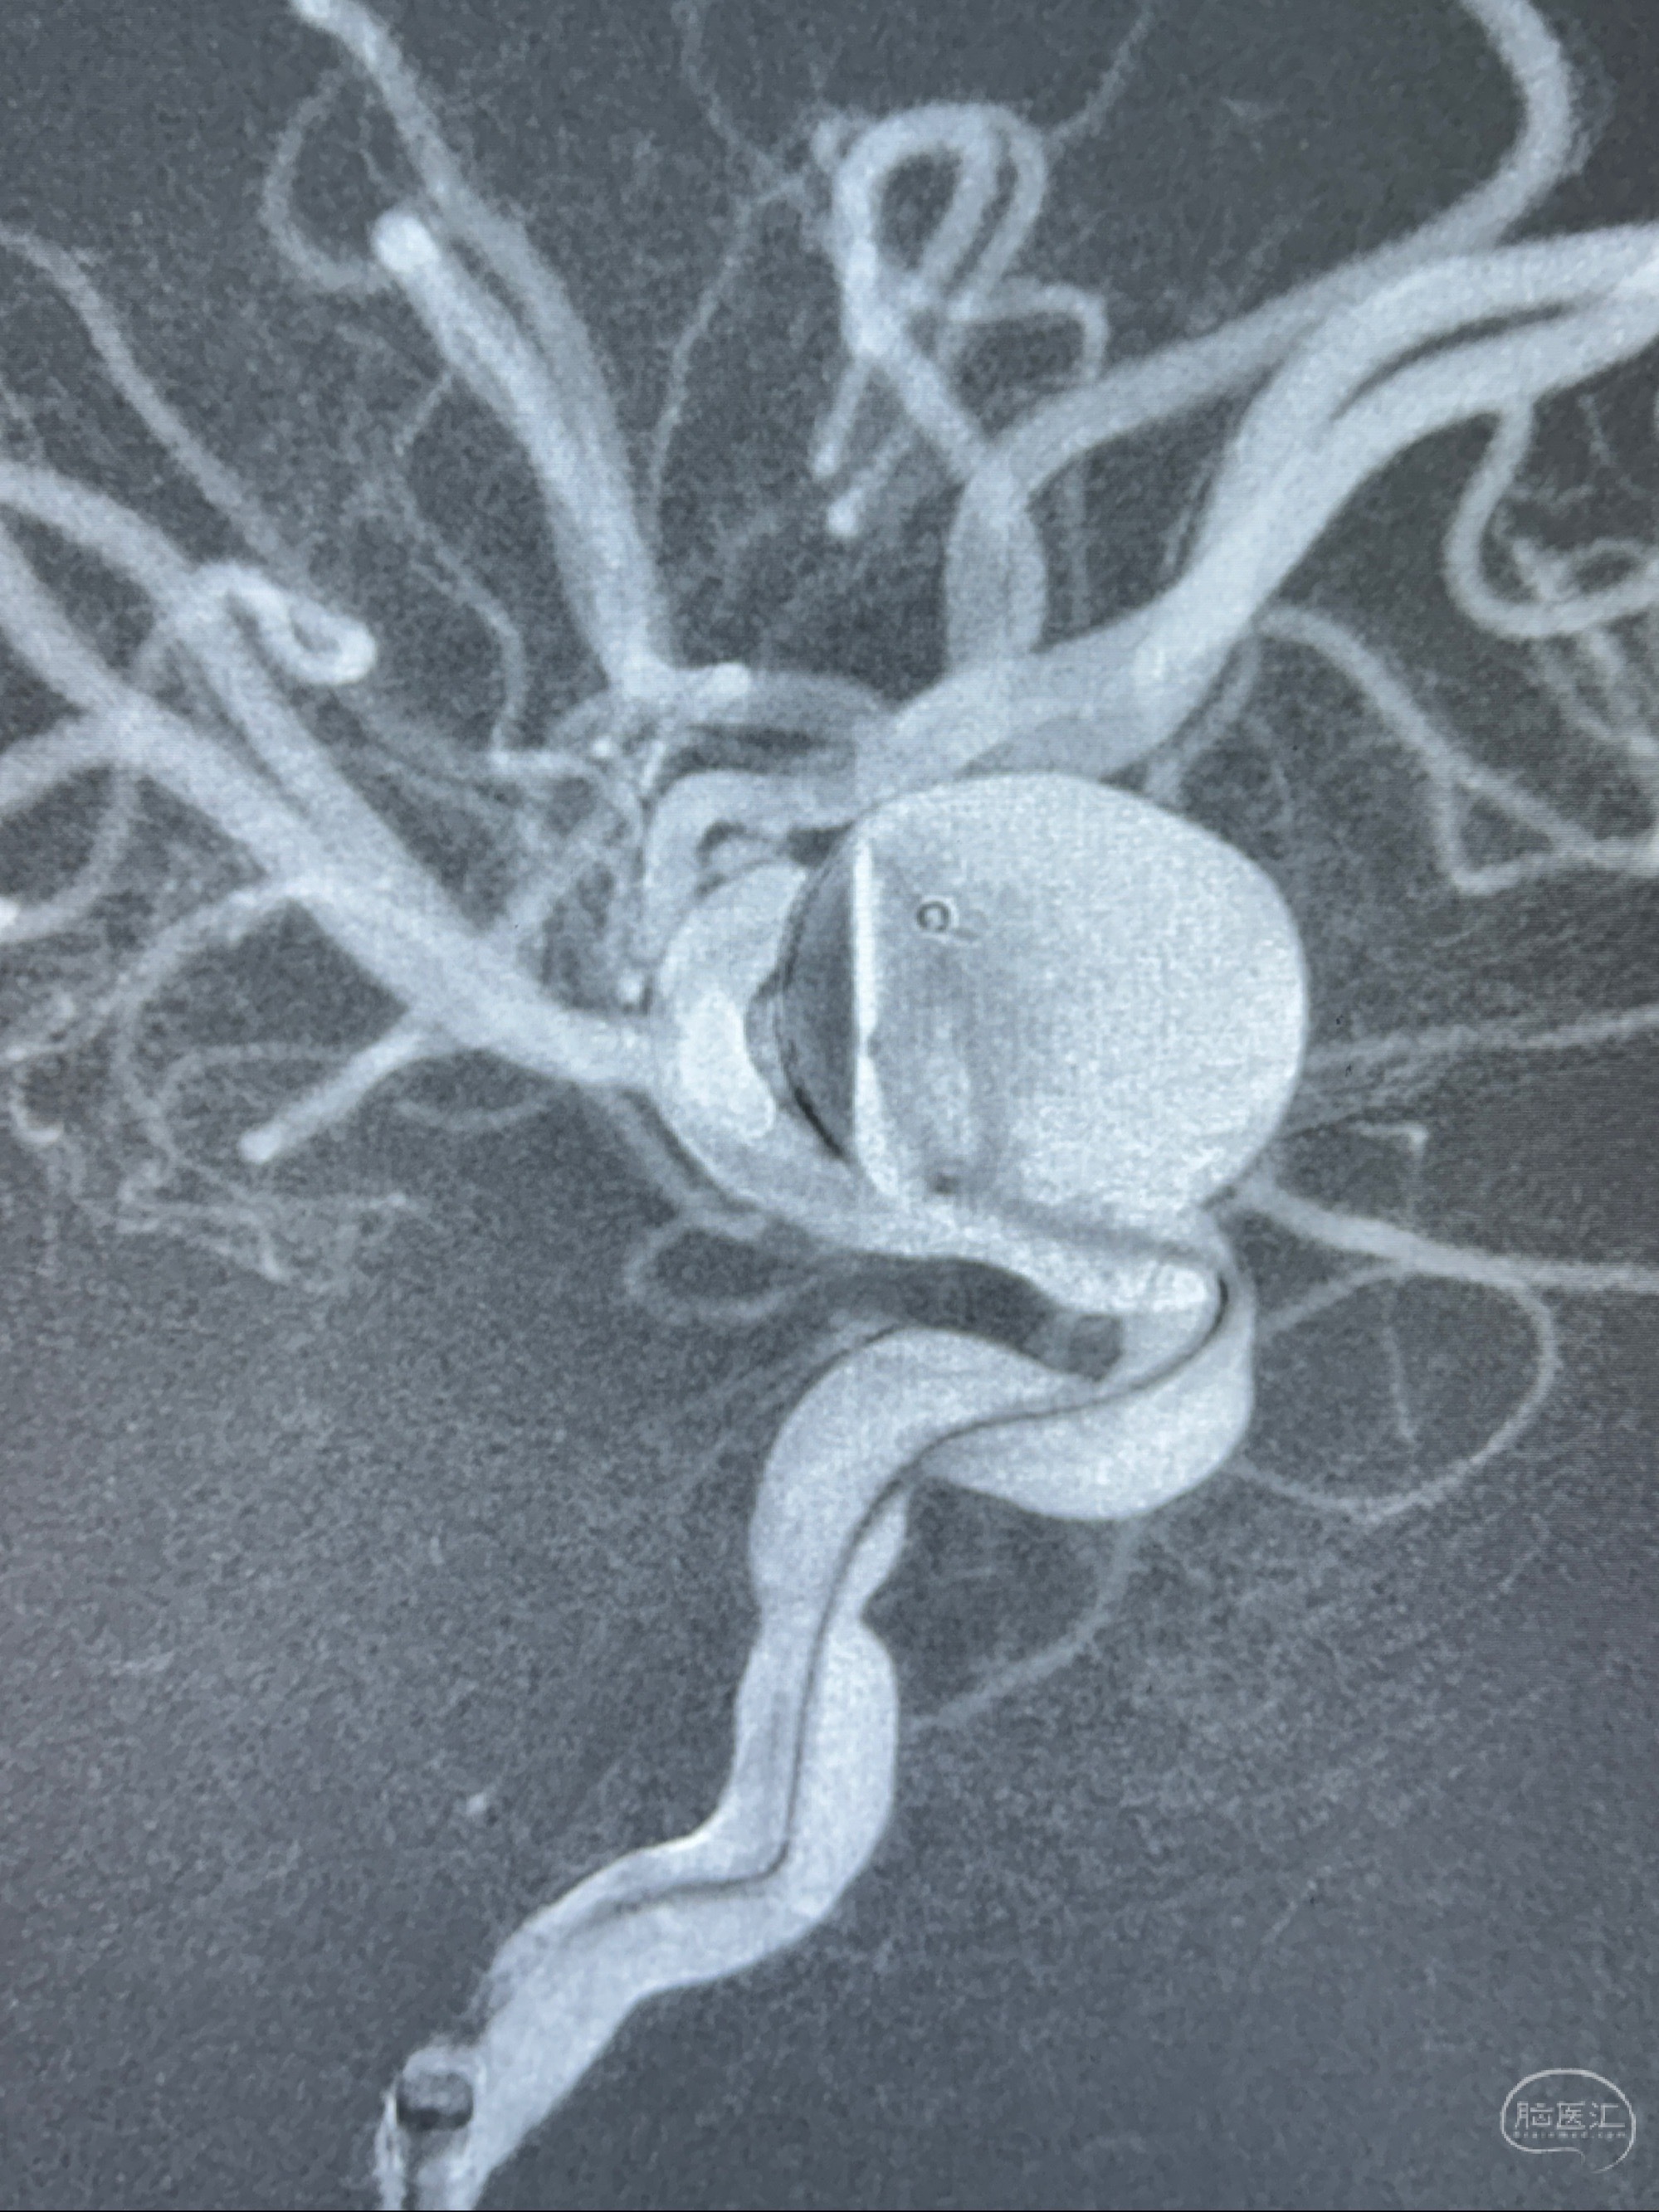

2023-12-27术后第十天复查DSA

支架贴壁佳,但可见射流,咋办?

2024-01-08全麻下再行植入密网支架一枚

Tubridge 4.5-35mm

支架植入顺利,贴壁佳,支架内血流通畅,动脉瘤内血液滞留明显